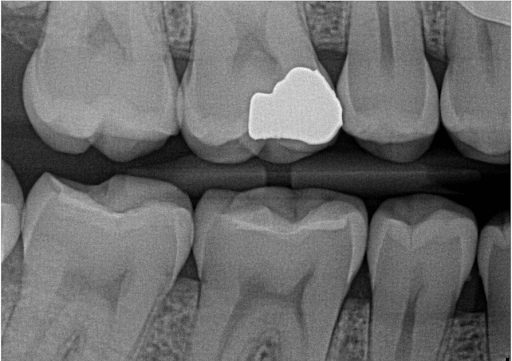

Digital Radiographs

We have digital radiographs . With digital radiographs, radiation is very low compared to conventional radiograph. It is quicker than conventional radiograph.

Digital radiograph